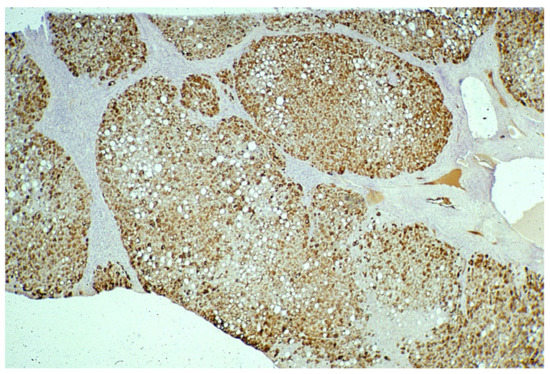

In Groups 1 and 2, all hepatocytes (up to 100%) could be positive (Figure 4a). The positivity of periportal hepatocytes are depicted globules or granules distributed in the whole cytoplasm (type I positivity), whilst in midlobular and centrolobular hepatocytes, the positivity appeared in the form of crescent-like or rectilinear double row arrays beneath the plasma membrane along the sinusoidal wall (type II positivity) (Figure 4b). The intensity of the staining was decreasing from zone 1 to zone 3 of the lobules. The AAT inclusions were negative for other secretory proteins, indicating that only the Z protein was retained [19].

Figure 4. Pi MZ liver specimen. All hepatocytes from adjacent lobules are positively stained for AAT (a) polyclonal AAT immunostaining × 2. The intensity of the staining decreases from zone 1, where the positivity involves the whole cytoplasm (type I positivity), to zones 2 and 3 where crescent like and rectilinear double rows pictures are clearly seen. (b) polyclonal AAT immunostaining × 100.